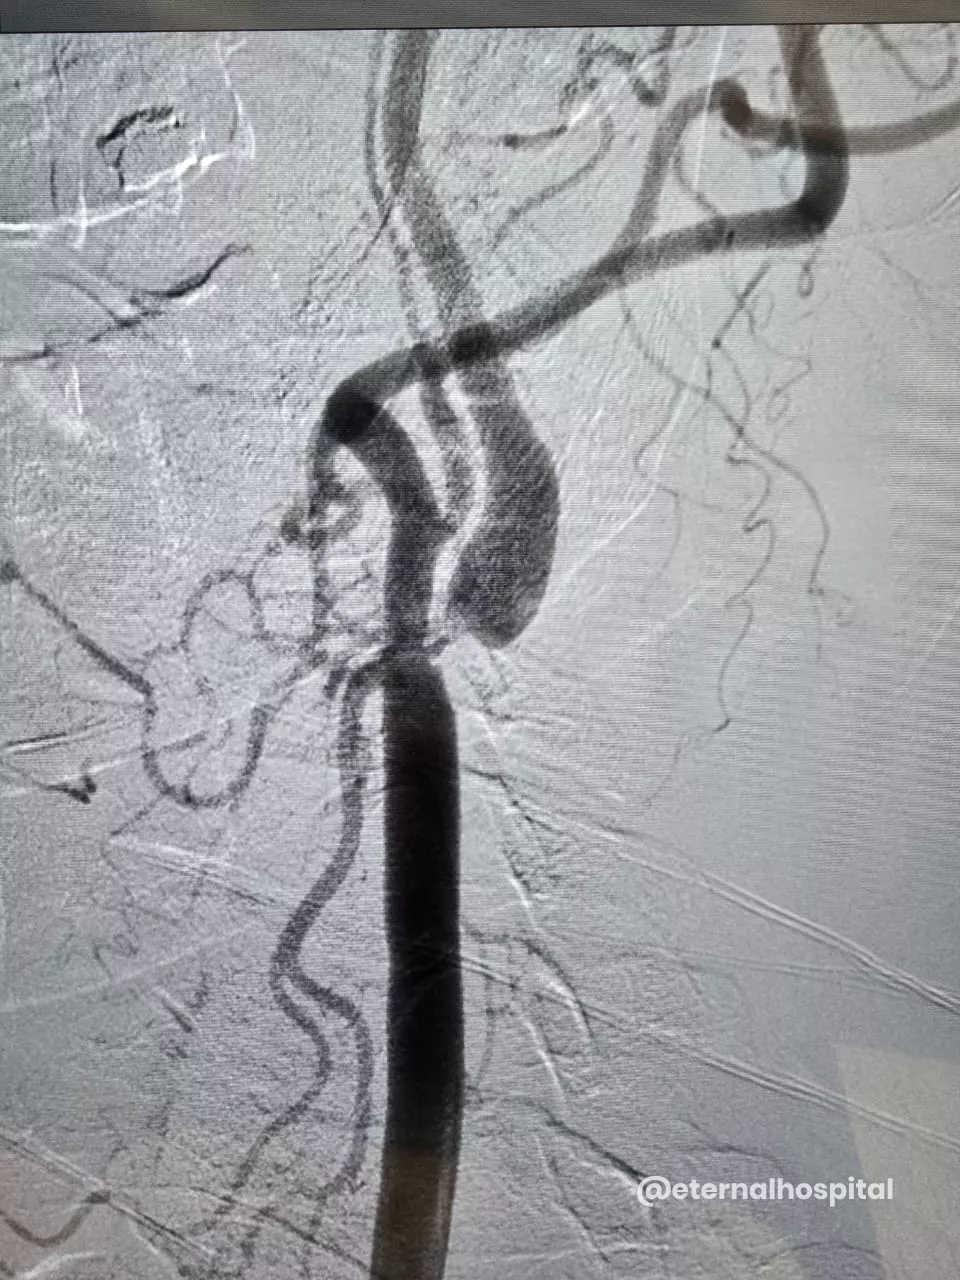

- The doctor numbs the insertion area, makes a small cut to the designated area, and inserts a thin tube (known as a catheter) into the artery.

- With the help of X-ray images, the thin tube is moved up to the narrowed section of the carotid artery.

- A tiny filter could be used to catch any loose debris.

- A small inflated balloon is used to expand the artery, and then the stent is fitted to keep the artery open.

- Afterward, the balloon and filter are taken out.